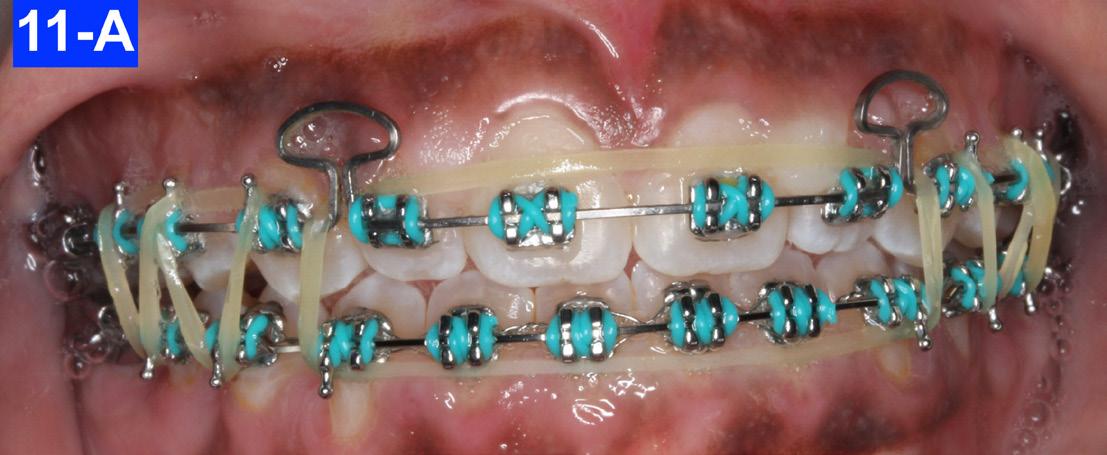

After twelve months of treatment, we inserted a Dr. Nanda Mushroom loop arch wire (019 x .025 CNA) in the maxilla to condense the spaces.7,8 The mushroom loop is opened 1.0 mm per month on both sides by pulling the arch wire back and placing a crisp bend back (cinch). It is advisable to heat treat and anneal the ends of the arch wire first. There was a .018 SS arch wire in the mandible. The patient continued with triangular and box elastics as previously (Figures 11-A, B, C).

Fig. 11-A: Mushroom AW, frontal view

Fig. 12-A: Retainers

Fig. 11-B: Mushroom AW, right lateral view